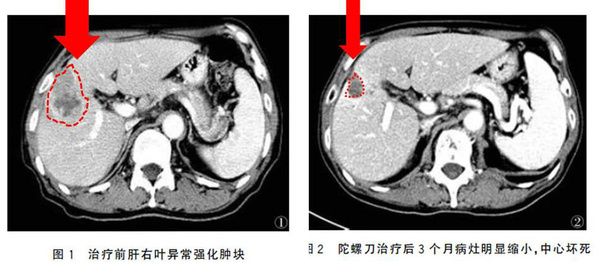

病例选择由临床病史结合影像诊断及肿瘤标志物检查确诊为转移性肝癌,肝功能Child分级A级,B级。Karnofsky评分(KPS评分)均为70分以上。治疗方法患者仰卧于带有真空负压定型袋的治疗定位床上,双手握头上手柄,平静呼吸下进行CT增强扫描,层厚5mm。获取定位图像后将图像传至TPS工作站,在计划系统内勾画出病灶及重要功能器官轮廓。勾画出大体肿瘤体积(GTV),计划靶体积(PTV)。PTV较GTV在Z轴方向外放范围为模拟机下患者平静呼吸状态膈肌运动幅度、一般为8~10mm;X、Y轴方向外放5mm。肝脏平均剂量<25Gy。选50%等剂量曲线作为处方剂量曲线,70%剂量线覆盖95%以上GTV,处方剂量每次3~5Gy,每周5次,共8~15次,肿瘤边缘总剂量40~45Gy,治疗在2~3周内完成。

陀螺刀治疗过程中,患者无明显肝部不适症状。实验室检查:白细胞总数下降,血小板下降,经升血、升血小板等对症治疗后均恢复正常。肝功能异常经保肝对症治疗后好转。胃肠道反应1级,放疗结束后1周恢复正常。无放射性肝损伤及放射性肝病发生。